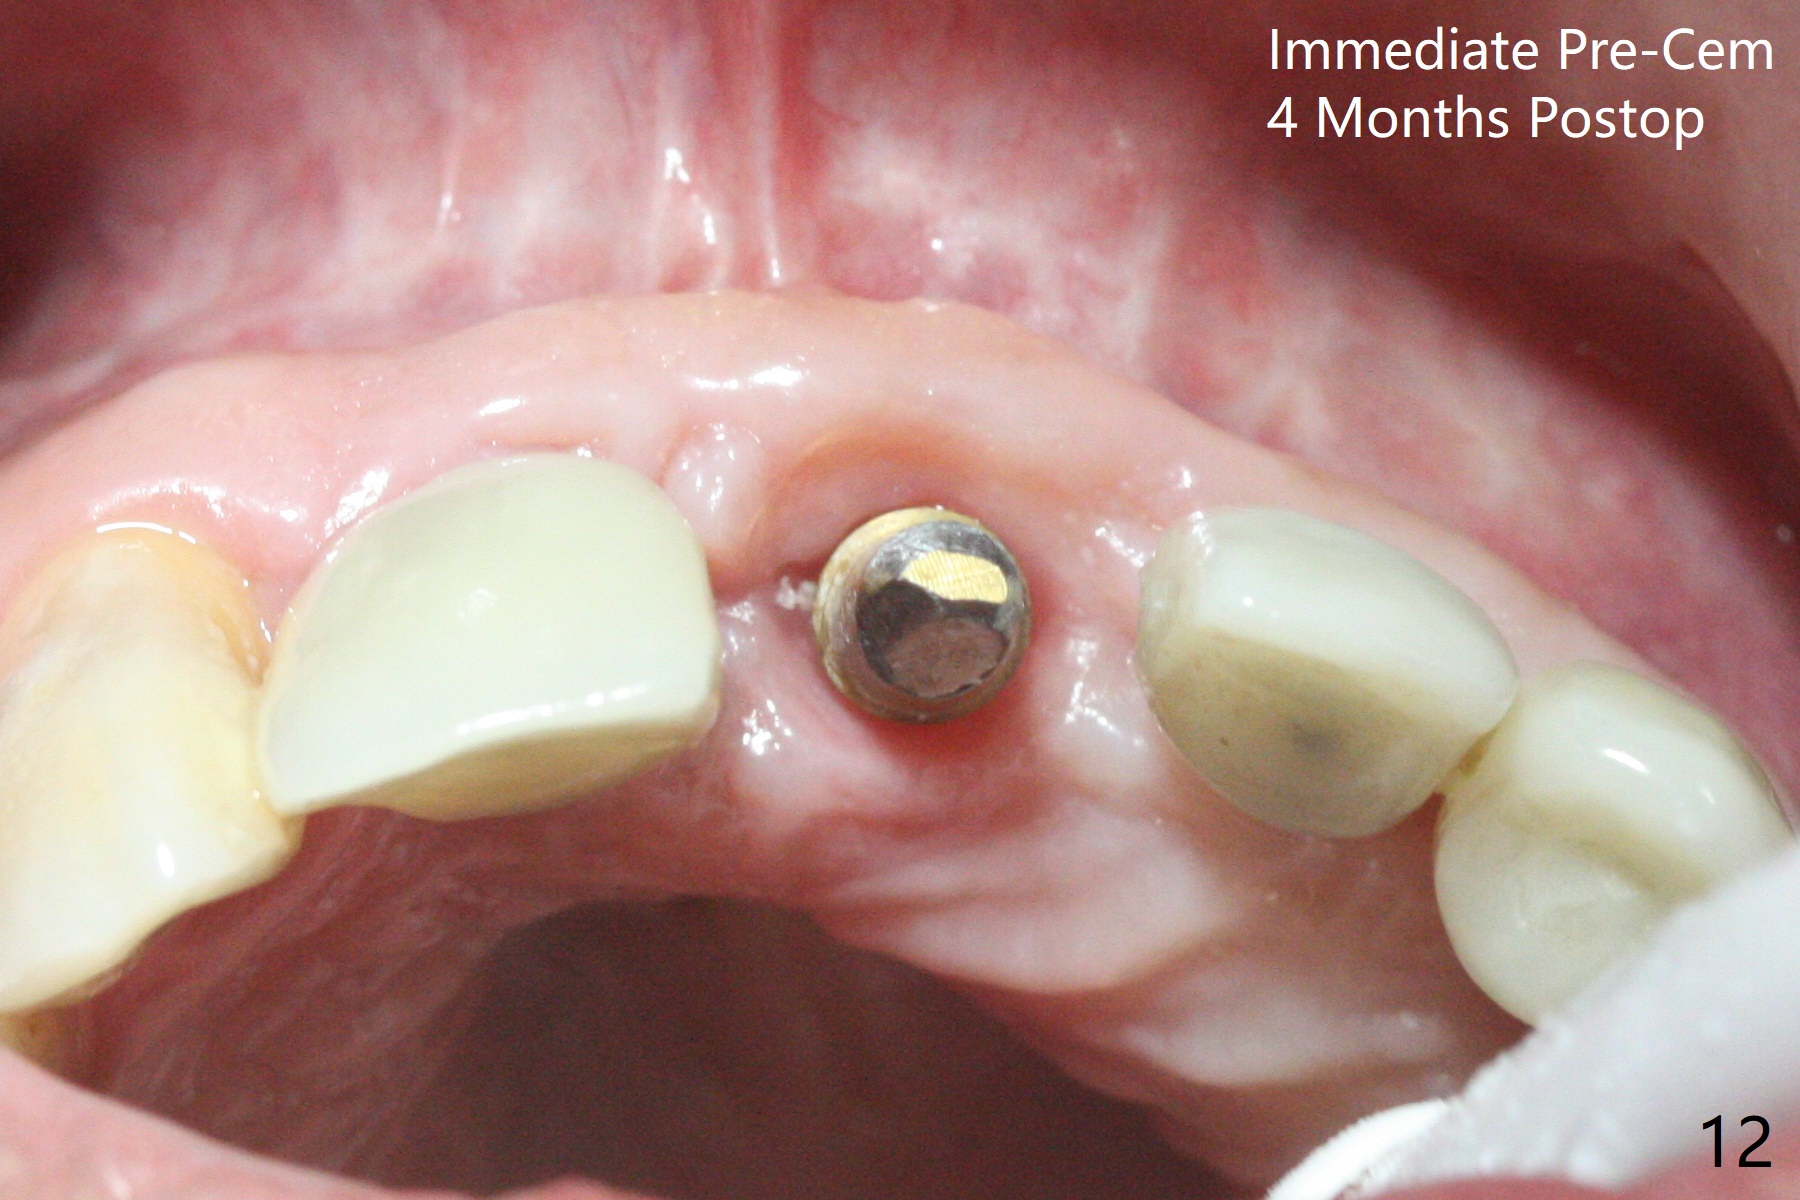

The implant access at #9 closes 1 week post implant fracture (Fig.1,4). There is mild gingival erythema at #10 (Fig.2,3 ^). There is bone around the fractured implant, which is palatally placed (Fig.5). The 2 mm implant is removed using 2/3 mm trephine bur. In spite of moving the osteotomy buccally, a 4.5x4 mm, 15 degree A-type angled abutment is installed for an immediate provisional following placement of a 3.5x10 mm implant (Fig.7, 25 Ncm). Sticky bone is placed (Fig.7 *) palatal to the implants at #9 and 10 (with thread exposure, Fig.6). While the majority of periodontal dressing remains in place (Fig.9,10), the suture in the exposed area appears to hold the papilla in place (Fig.8 <). Herpetic infection develops in the palate (Fig.9). Two months later, the gingiva at #10 is healthy; it appears that the implant threads are covered by bone graft. The immediate provisional (fabricated before suture) keeps the gingiva in an ideal position for impression of final restoration. It appears that the access hole is in a right area for screw retained restoration. The gingival cuff is healthy immediate pre-cementation, 4 months postop (Fig.12,13). The lab does not make access hole for the final crown (Fig.14). The implant remains subcrestal 4 months postop (Fig.15). Since the shade of the crown is off, the abutment remains un-torqued and the crown is cemented with temp bond. The implant threads at #10 seem to be covered by bone graft 4 months postop (Fig.16).